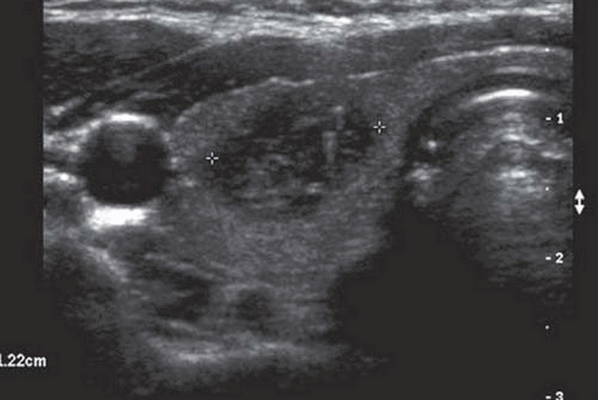

Лучший диагностический подход. Хорошо отграниченное, диффузное увеличение щитовидной железы с неоднородным узловым внешним видом. Кальцификации, фиброз, кистозные изменения и кровоизлияния приводят к появлению гетерогенных изображений структуры железы

Морфология. Четко выраженное диффузное увеличение щитовидной железы в висцеральном пространстве шеи. Сонные пространства смещены от средней линии; трахея сдавлена между увеличенными долями щитовидной железы

Серошкальное УЗИ. Множественные узлы, двустороннее диффузное вовлечение обеих долей. Солидные узлы часто изоэхогенные, с небольшой долей гипоэхогенных (5%). Несмотря на то, что они не инкапсулированы, узлы резко очерчены и имеют ореол - хало, который состоит из сосудов и сжатой щитовидной железы. Гетерогенная эхоструктура с внутренним детритом, перегородками, солидными и кистозными участками. Сплошная часть внутри узлы часто представляет собой сгусток крови. Плотное затенение кальцификации (криволинейное, дисморфное, грубое) ± множественное. Узлы с артефактом из хвоста кометы очень напоминают коллоидный узел (имитирует микрокальцификацию). Кистозный компонент возникает из-за дегенерации, кровоизлияния или коллоида в узле. Фоновые паренхиматозные эхоструктуры щитовидной железы являются грубыми и неоднородными (тонкие яркие эхосигналы в нормальной железе).

Цветовой допплер показывает, что периферическая васкуляризация более выражена, чем интранодулярная сосудистая сеть. Септы и интранодулярные солидные порции являются бессосудистыми (чаще представлена кровяным сгустком).